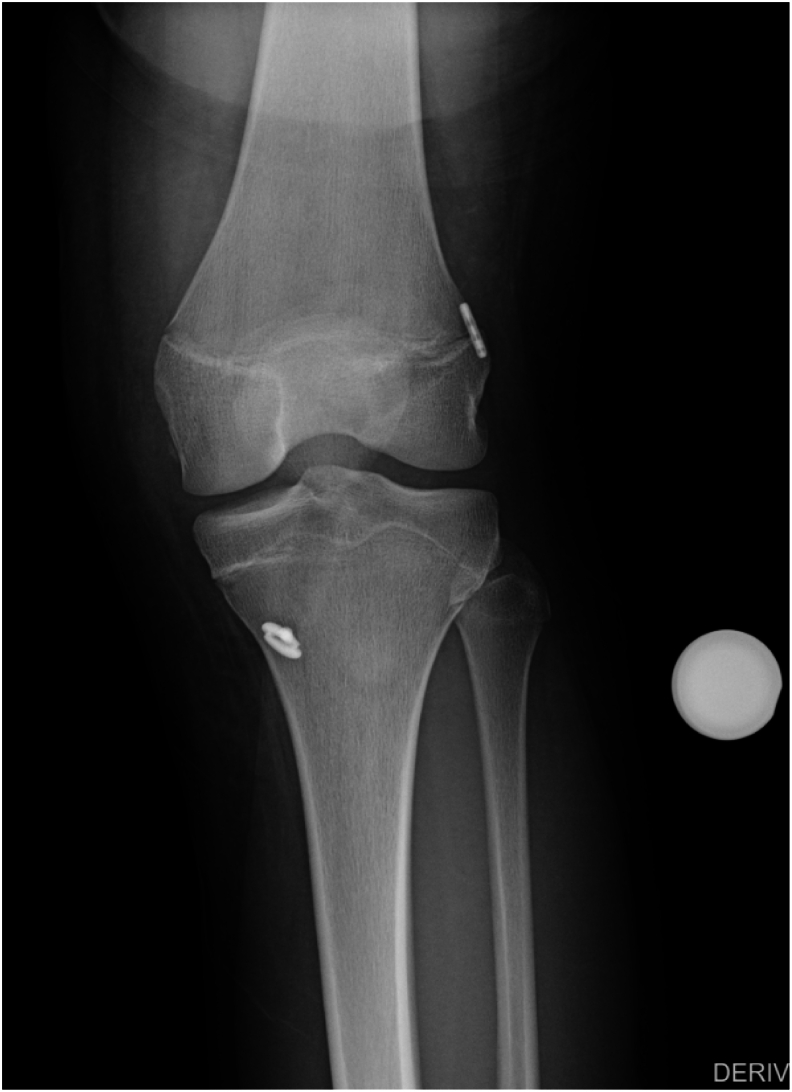

Lateral extra-articular tenodesis (LET), as an adjunct to anterior cruciate ligament (ACL) reconstruction, is gaining popularity among pediatric and sports medicine orthopaedic surgeons for the treatment of ACL injury, especially in the female, hyperflexible, and high-risk athlete population. The addition of LET or anterolateral ligament (ALL) reconstruction is typically recommended at the time of index ACL reconstruction surgery and is performed after the ACL graft is tensioned. Rotational instability has been described in cases where the ACL graft was malpositioned too vertically, and in those cases, ACL revision is indicated. In our case, ACL reconstruction was performed in isolation in a hyperflexible, high-risk (volleyball) female athlete, and she had persistent complaints of rotational instability despite an intact and well-positioned ACL graft on magnetic resonance imaging (MRI) scan. She demonstrated excessive internal rotation of the tibia in relation to the femur and exhibited symptomatic anterolateral instability on clinical examination, with a negative pivot shift but pain on internal rotation stress. She underwent a second surgery consisting of isolated modified Lemaire LET after examination under anesthesia (EUA) demonstrated negative Lachman and pivot shift. Second-look arthroscopy demonstrated an intact quadriceps autograft ACL graft. She recovered uneventfully, and her rotational instability problem was resolved. She returned to sports 12 months after the surgery and has been pleased with her result.

Key concepts: (1)Lateral extra-articular tenodesis (LET) can be added to increased rotational stability in the setting of anterior cruciate ligament (ACL) reconstruction.(2)Although typically added during the index procedure, it can be successfully completed later if needed.(3)The ACL confers both anteroposterior and rotational stability to prevent excessive anterior translation and excessive internal rotation of the tibia with respect to the femur.(4)LET can augment the ACL graft in preventing rotational instability in the setting of an ACL-deficient knee.